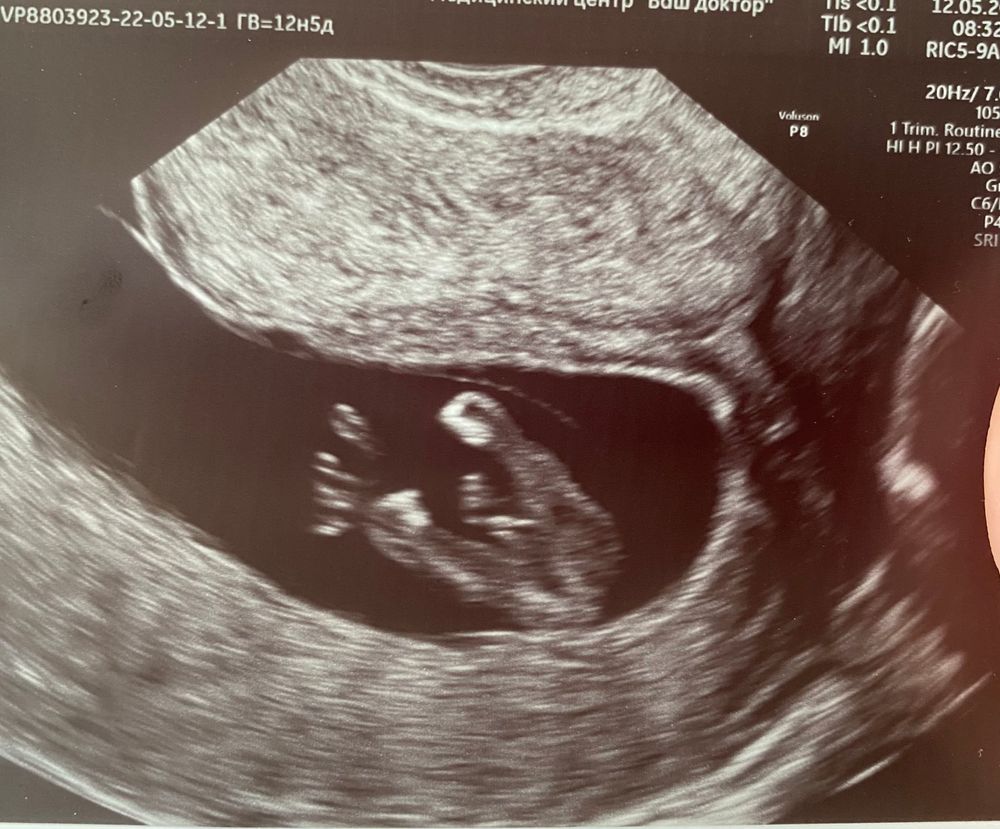

пол малыша в 12 недель

Как думаете можно ли определить пол на таком сроке? И на каком сроке вы узнали? И по фотке как думаете кто там?))) Хочется поскорее узнать❤️